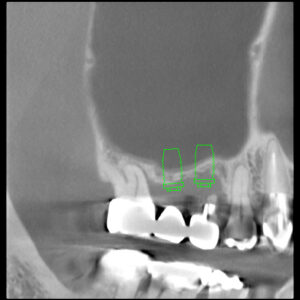

もともと「インプラントをするための骨がないので難しい」といわれた患者さんでした。

当院でのラテラルスリット法はサイナスリフトの改良法でより腫れにくくスピーディーにオペができます。

インプラント体が十分に骨と結合したか否かは

ペリオテストという機器を使い、数値化するので間違いがありません。